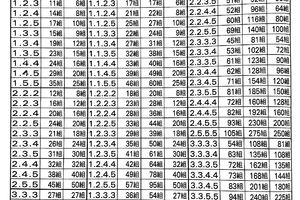

肋骨損傷的分級

首先醫生會對患者查體,胸廓擠壓試驗呈現陽性體徵,並且在咳嗽、呼吸時有明顯的胸部疼痛,可懷疑有肋骨骨折。根據損傷的原因,程度和類型,損傷又分為三級:

輕度:

損傷類型:輕微,例如磕碰到東西。

症狀:胸部伴有輕度疼痛不適,無明顯淤青或腫脹,觸感柔軟,無呼吸問題。

醫生建議:一部分患者的疼痛會消失,如果不適持續存在,可考慮進行胸部X光檢查,如果胸部X光檢查正常,但依然有持續疼痛或壓痛,可考慮進行CT檢查和超聲評估。

中度:

損傷類型:較嚴重,例如跌倒。

症狀:呼吸伴有明顯疼痛,胸部區域有明顯壓痛,以及淤青和腫脹。

醫生建議:這時候需要明確骨折跡象,可考慮胸部X光檢查,但胸痛往往與呼吸問題相關,建議進行胸部CT掃描。由於有一些肋骨骨折無移位,X光片難以確認,需要進一步CT橫斷面掃描。

嚴重:

損傷類型:嚴重,例如從高處墜落,或者汽車,電動車、摩托車造成的交通事故,多為嚴重的撞擊傷。

症狀:伴有嚴重的持續疼痛,並伴有胸部壓痛、淤青和腫脹。胸部體檢可發現明顯異常。

醫生建議:需要胸部CT掃描來評估胸壁損傷和任何相關的內傷。

由此可見,CT掃描檢查是診斷肋骨骨折的最佳手段。有些骨折X光不一定能看得清。肋骨骨折可由輕微的碰撞引起,也可由嚴重的車禍造成,最容易發生骨折的在第4-7肋骨,不僅因為它們長而且細,並且缺乏上方1-3肋骨的鎖骨和肩胛骨的保護。往下則是第10-12肋骨,它們的一端是懸空的,不固定在任何骨頭上,彈性大,也不容易骨折。